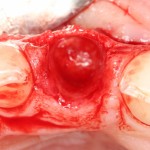

После удаления зуба и сопутствующей гранулемы, остается большая по размеру лунка с тонкой и поврежденной воспалительным процессом вестибулярной стенкой:

Первым делом, необходимо определиться с подготовкой лунки под имплантат. Проверить правильность позиционирования лунки можно с помощью аналогов имплантов, входящих в комплект XiVE Dentsply Implants: